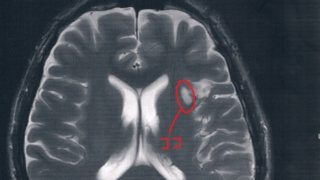

GLIOMA:悪性転化が無いかどうかの確認検査

前回10月の定期検査で腫瘍が大きくなってる↓かもしれないとの診断で検査時期を早めて、造影剤も注射してMRI検査をすることに。結果から言って、造影剤の入り込みも無く悪性転化は無いとのこと。言語検査に結果も特に問題無し。まあ、SLTA標準失語症...